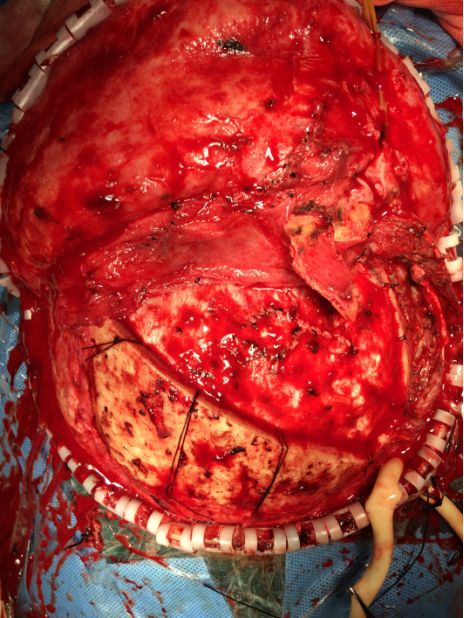

中年男性,车祸致头面部流血1小时入院。体查:神志模糊,右侧额部眉间鼻根部见十余厘米长开放性伤口,其内见多发碎骨片,伤口内活动性出血,口鼻流血,四肢刺激可定位,GCS评分:E2V2M5=9分。

术前外观